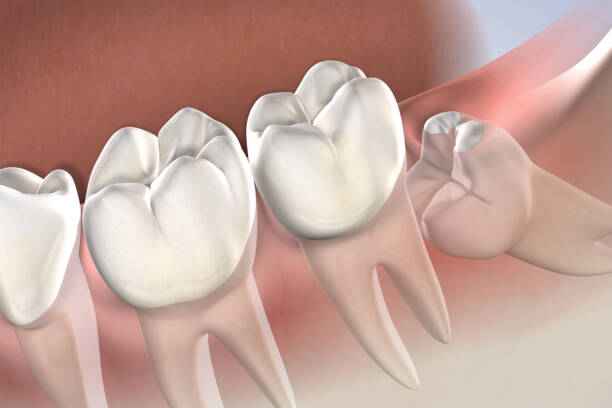

ضرس العقل هو الضرس الثالث والأخير في كل ربع من أرباع الفم، ويُعرف علميًا باسم الضرس الطاحن الثالث. يتميز بموقعه الخلفي العميق، ما يجعله أكثر عرضة للمشكلات مقارنة ببقية الأسنان. غالبًا ما يكون بزوغه غير مكتمل أو منحرفًا بسبب ضيق المساحة، الأمر الذي يؤدي إلى سلسلة من المشكلات المتتابعة. وهنا تبدأ اعراض ضرس العقل في الظهور تدريجيًا، كتنبيه بيولوجي بأن هذا الضرس لا يسلك المسار الطبيعي للنمو. ومع استمرار الضغط والاحتكاك، تتفاقم اعراض ضرس العقل وتتحول من مجرد انزعاج إلى ألم حاد قد يؤثر على جودة الحياة اليومية.

عادةً ما تنبثق ضروس العقل بين سن السابعة عشرة والخامسة والعشرين، وهي مرحلة يكتمل فيها نمو الفك لدى معظم الأشخاص. إلا أن هذا التوقيت ليس قاعدة صارمة، فقد تتأخر أو تتقدم حسب العوامل الوراثية وبنية الفك. في هذه الفترة العمرية تحديدًا، تبدأ اعراض ضرس العقل في الظهور عند شريحة واسعة من الشباب، خاصة مع بزوغ جزئي أو مائل. إن تجاهل اعراض ضرس العقل خلال هذه المرحلة قد يؤدي إلى التهابات مزمنة ومضاعفات يصعب علاجها لاحقًا.

يُعد ضرس العقل آخر الأسنان بزوغًا في الفم، وغالبًا ما يظهر في مرحلة عمرية حساسة يتغير فيها توازن الفك ونمط الإطباق. في معظم الحالات يبدأ ظهوره ما بين سن السابعة عشرة والخامسة والعشرين، إلا أن هذا الإطار الزمني ليس قاعدة ثابتة. قد يتأخر ظهوره لدى بعض الأشخاص إلى ما بعد الثلاثين، وقد لا يظهر نهائيًا لدى آخرين. خلال هذه المرحلة العمرية تبدأ اعراض ضرس العقل بالظهور تدريجيًا، فتارة تكون خفيفة وتارة أخرى شديدة ومربكة. إن تزامن النمو العظمي المحدود للفك مع محاولة بزوغ الضرس هو السبب الأساسي في ظهور اعراض ضرس العقل بشكل مفاجئ أو متكرر.

شكل ضرس العقل

يختلف شكل ضرس العقل من شخص لآخر، إلا أنه غالبًا ما يتميز بحجم أكبر وجذور أكثر تعقيدًا مقارنة ببقية الأضراس. قد يكون مكتمل التكوين أو مشوهًا جزئيًا، وقد يظهر بشكل عمودي أو مائل أو حتى أفقي. هذه الاختلافات الشكلية تلعب دورًا مباشرًا في حدة اعراض ضرس العقل. ومن أبرز السمات الشكلية الشائعة:

• بزوغ جزئي يترك جزءًا من الضرس مغطى باللثة.